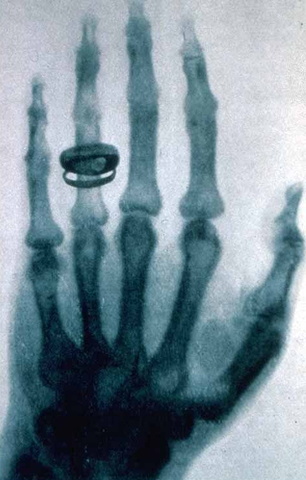

El físico alemán Wihelm Conrad Roentgen descubrio los rayos X mientras realizaba experimentos con tubos de vacío y un generador electrico.

El 22 de noviembre del 1895 se realiza el artículo sobre "Una nueva clase de rayos X" y se presenta el 28 de diciembre del mismo año, luego se propagó la noticia por todo el mundo,

Roentgen realize su primera demostración de los rayos X ante la Sociedad Médica Física de Wurzburg.

14 días despues de que Roentgen anunciara su descubrimbiento el Dr. Otto Walkhoff de Braunscheweing Alemania, realize la primera radiografía dental. Su tiempo de exposición fue de 23 min.